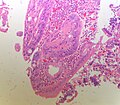

Ampulla of Vater

The ampulla of Vater, also hepatopancreatic ampulla, is found in the duodenum. It has a unique histology and is a relatively common site of disease, when duodenal pathology is considered.

Ampullary tumours

Ampullary adenoma

Microscopic

Features:

- +/-Paneth cells - may be prominent.[3]

- Similar to adenoma of colon - with:

- Less pseudostratification.

- Finer chromatin pattern.